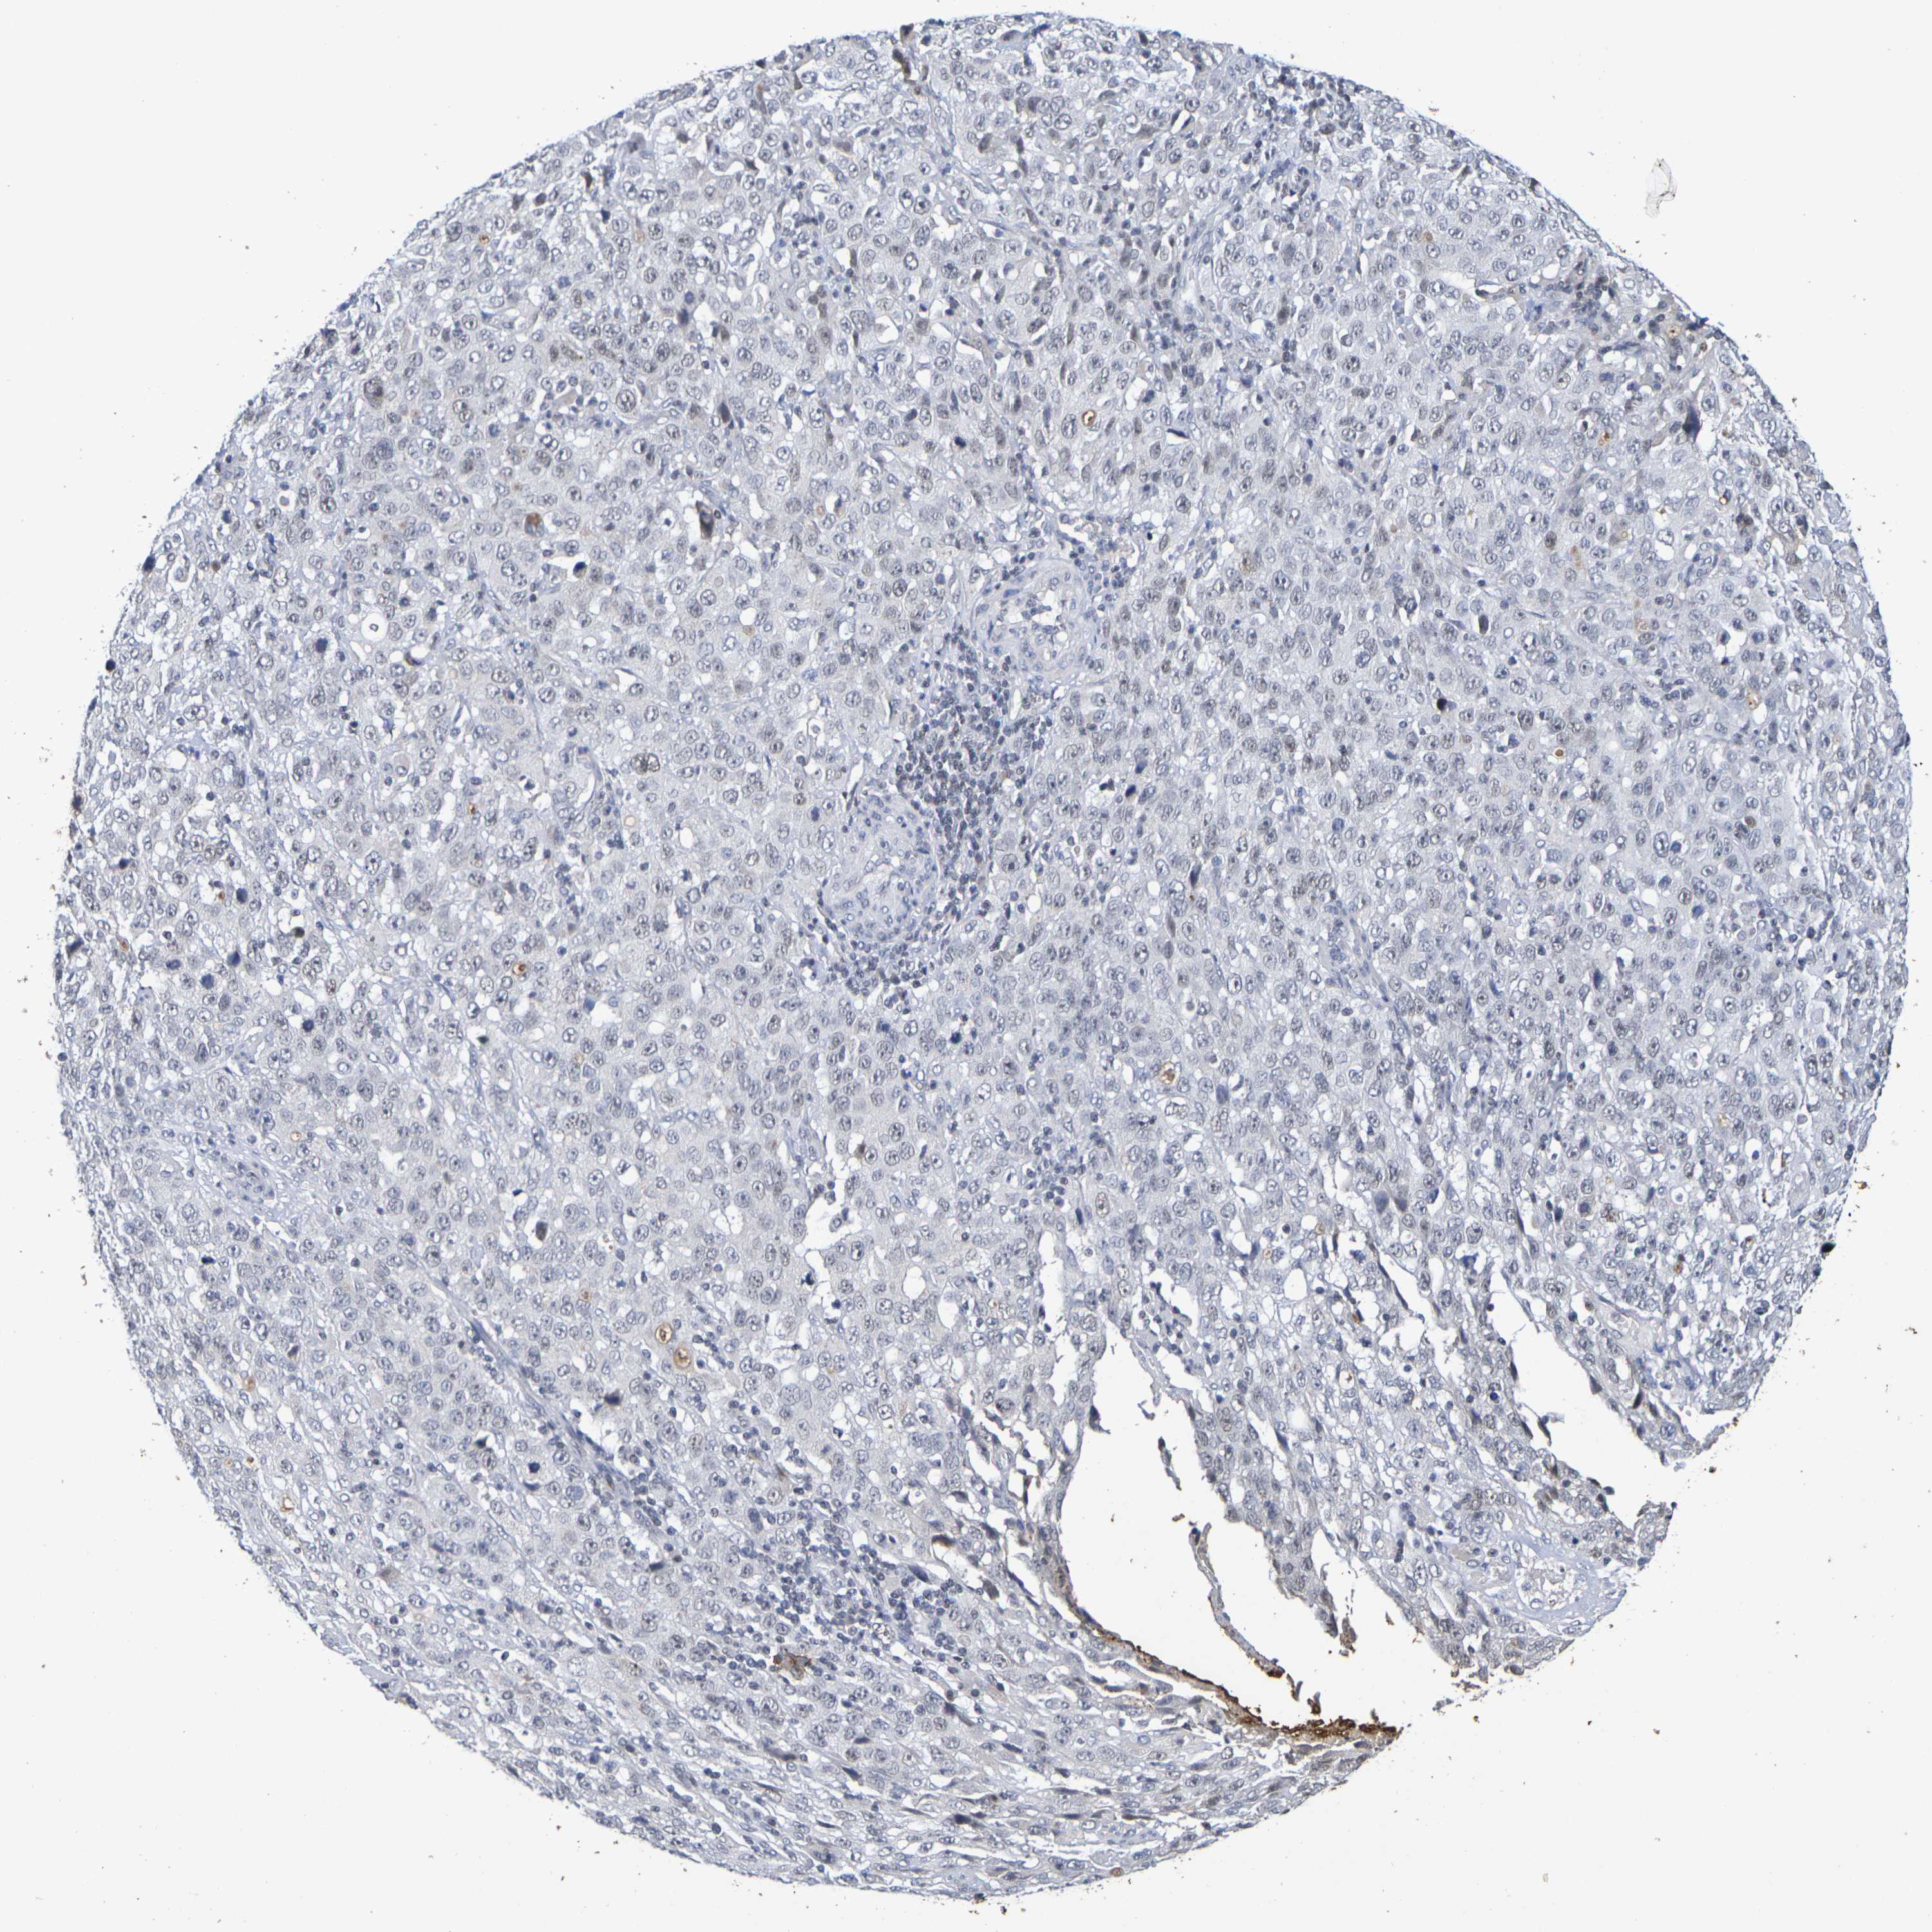

STOMACH CANCER - Protein expressioni

A mouse-over function shows sample information and annotation data. Click on an image to view it in a full screen mode. Samples can be filtered based on level of antibody staining by selecting one or several of the following categories: high, medium, low and not detected. The assay and annotation is described here.

Note that samples used for immunohistochemistry by the Human Protein Atlas do not correspond to samples in the TCGA dataset.

Antibody stainingi

Antibody staining in the annotated cell types in the current human tissue is reported as not detected, low, medium, or high, based on conventional immunohistochemistry profiling in selected tissues. This score is based on the combination of the staining intensity and fraction of stained cells.

Each image is clickable and will lead to virtual microscopy that enables deeper exploration of all samples and also displays staining intensity scores, fraction scores and subcellular localization as well as patient and tissue information for each sample.

Antibody HPA001907

Antibody HPA002735

Antibody CAB010451

Antibody CAB080271

Staining

High

Medium

Low

Not detected

Intensity

Strong

Moderate

Weak

Negative

Quantity

>75%

75%-25%

<25%

None

Location

Nuclear

Cytoplasmic/membranous

Cytoplasmic/membranous,nuclear

Adenocarcinoma, NOS

Adenocarcinoma, High grade